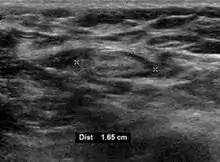

- Absence of the fatty hilum

- Increased focal cortical thickness greater than 3 cm

- Doppler ultrasonography that shows hyperaemic blood flow in the hilum and central cortex and/or abnormal (non-hilar cortical) blood flow.[24]

On ultrasound, B-mode imaging depicts lymph node morphology, whilst power Doppler can assess the vascular pattern.[26] B-mode imaging features that can distinguish metastasis and lymphoma include size, shape, calcification, loss of hilar architecture, as well as intranodal necrosis.[26] Soft tissue edema and nodal matting on B-mode imaging suggests tuberculous cervical lymphadenitis or previous radiation therapy.[26] Serial monitoring of nodal size and vascularity are useful in assessing treatment response.[26]

Lymphadenopathy of the axillary lymph nodes can be defined as solid nodes measuring more than 15 mm without fatty hilum.[34] Axillary lymph nodes may be normal up to 30 mm if consisting largely of fat.[34]

Lymphadenopathy of more than 1.5–2 cm increases the risk of cancer or granulomatous disease as the cause rather than only inflammation or infection. Still, an increasing size and persistence over time are more indicative of cancer.[37]